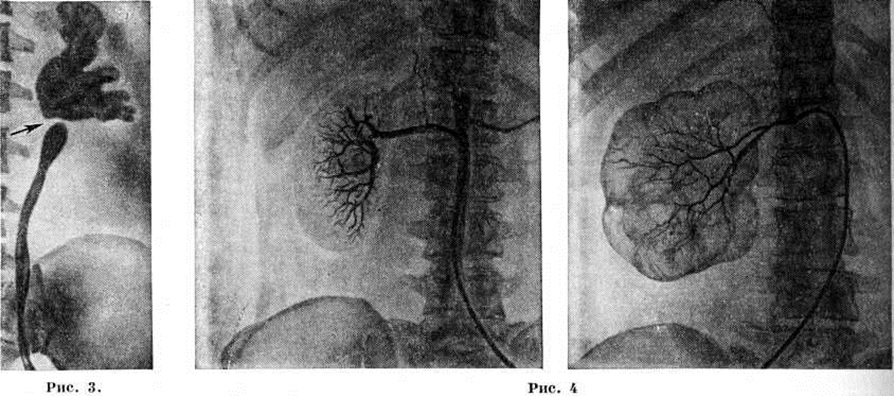

Изображения на урограммах при Гидронефроз имеют разнообразную форму — от умеренной пиелоэктазии до большой круглой или овальной полости с резко расширенными чашечками; полости с чёткими ровными краями, что отличает Гидронефроз от пионефроза. На уретерограмме видны зоны стриктур, перегибов, атоничные мочеточники, а также обтекаемые контрастным веществом препятствия в нем, например, камни, опухоль. Поперечный перерыв тени в области лоханочно-мочеточникового сегмента характерен для клапана, добавочного сосуда (рисунок 3).

Рисунок 3.

Рентгенограмма почки и мочеточника при гидронефрозе на почве добавочного сосуда (стрелкой указан дефект наполнения мочеточника в месте сдавления его добавочным сосудом).

Рисунок 4.

Селективная почечная артериограмма: слева — нормальная почка; справа — при гидронефрозе (обеднение сосудистого рисунка, уменьшение калибра основного ствола и внутриорганных ветвей почечной артерии). На фоне позвоночника виден введённый в аорту катетер.

Анализ мочи, раздельно взятой из почек, и бактериологических исследование её с определением чувствительности микрофлоры к антибиотикам при инфицированном Гидронефроз дополняют клинической, диагностику. Селективную артериографию (рисунок 4) для диагностики Гидронефроз производят сравнительно редко с целью уточнения стадии процесса изучения сосудистого рисунка почки, а также выявления добавочного сосуда (смотри Почечная ангиография). Изредка применяют чрескожную пункционную антеградную пиелографию (рисунок 5). Радиоизотопная ренография существенно дополняет рентгено л. исследование, особенно при двустороннем Гидронефроз, когда удаётся выявить сторону наибольшего поражения (смотри Ренография радиоизотопная).